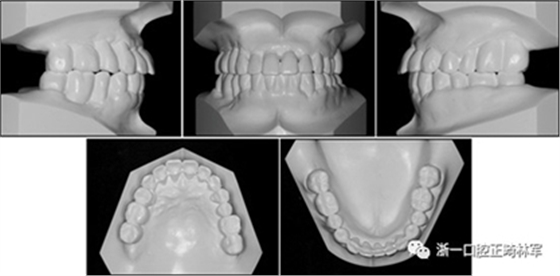

圖2. 治療前牙齒石膏模型

在治療結(jié)束時,通過拔除下頜側(cè)切牙,間隙閉合和推上頜牙列向遠(yuǎn)中,實現(xiàn)了前牙良好的對齊,尖牙I類關(guān)系以及合適的覆合和覆蓋?;颊叩膫?cè)面貌輪廓得到改善,并且她的嘴唇不適得到緩解。下頜右側(cè)第二磨牙直立,后牙被修復(fù)并恢復(fù)穩(wěn)定咬合(圖10和圖11)。牙周治療和牙周病的控制導(dǎo)致牙周袋深度的穩(wěn)定,并且在探測時沒有出血。

圖11.治療后牙齒的石膏模型

治療后頭影測量分析顯示上頜切牙的傾斜和唇部相對于E線的位置都得到改善(表II)。治療前后頭影測量圖的疊加顯示上頜和下頜切牙的向后移動伴隨著上頜切牙的推入。垂直維度在跨學(xué)科正畸綜合治療后被保持。三維模型的疊加顯示了上頜牙列的遠(yuǎn)中移動,下頜前牙的回縮和上頜右側(cè)尖牙的推入(圖14)。